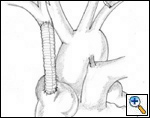

Figure 5A & B. (A) Intraluminal shunt. (B) Extraluminal shunt during reconstruction of the superior vena cava. Surgical strategy and shunting techniques: Every effort should be attempted to reduce clamping time as much as possible, in particular when the SVC system is not completely occluded before the operation. It has been reported that up to 45 to 60 minutes of complete clamping is usually tolerated with the appropriate pharmacological support. For lung cancer resection, the vascular step should be always performed before any other reconstructive procedure of the airway. For mediastinal tumors involving the upper lobes, the dissection should be performed from the left to the right side; the right part of the excision is usually performed after vascular reconstruction, in particular when a lobectomy is required. Intravascular or extravascular shunts (Figure 5) may be used to reduce the effects of vascular clamping during resection and reconstruction of the SVC[4]. However, thrombosis of the shunt may occur; furthermore, these devices occupy space in the operative field making the anastomosis more difficult.

![]() |